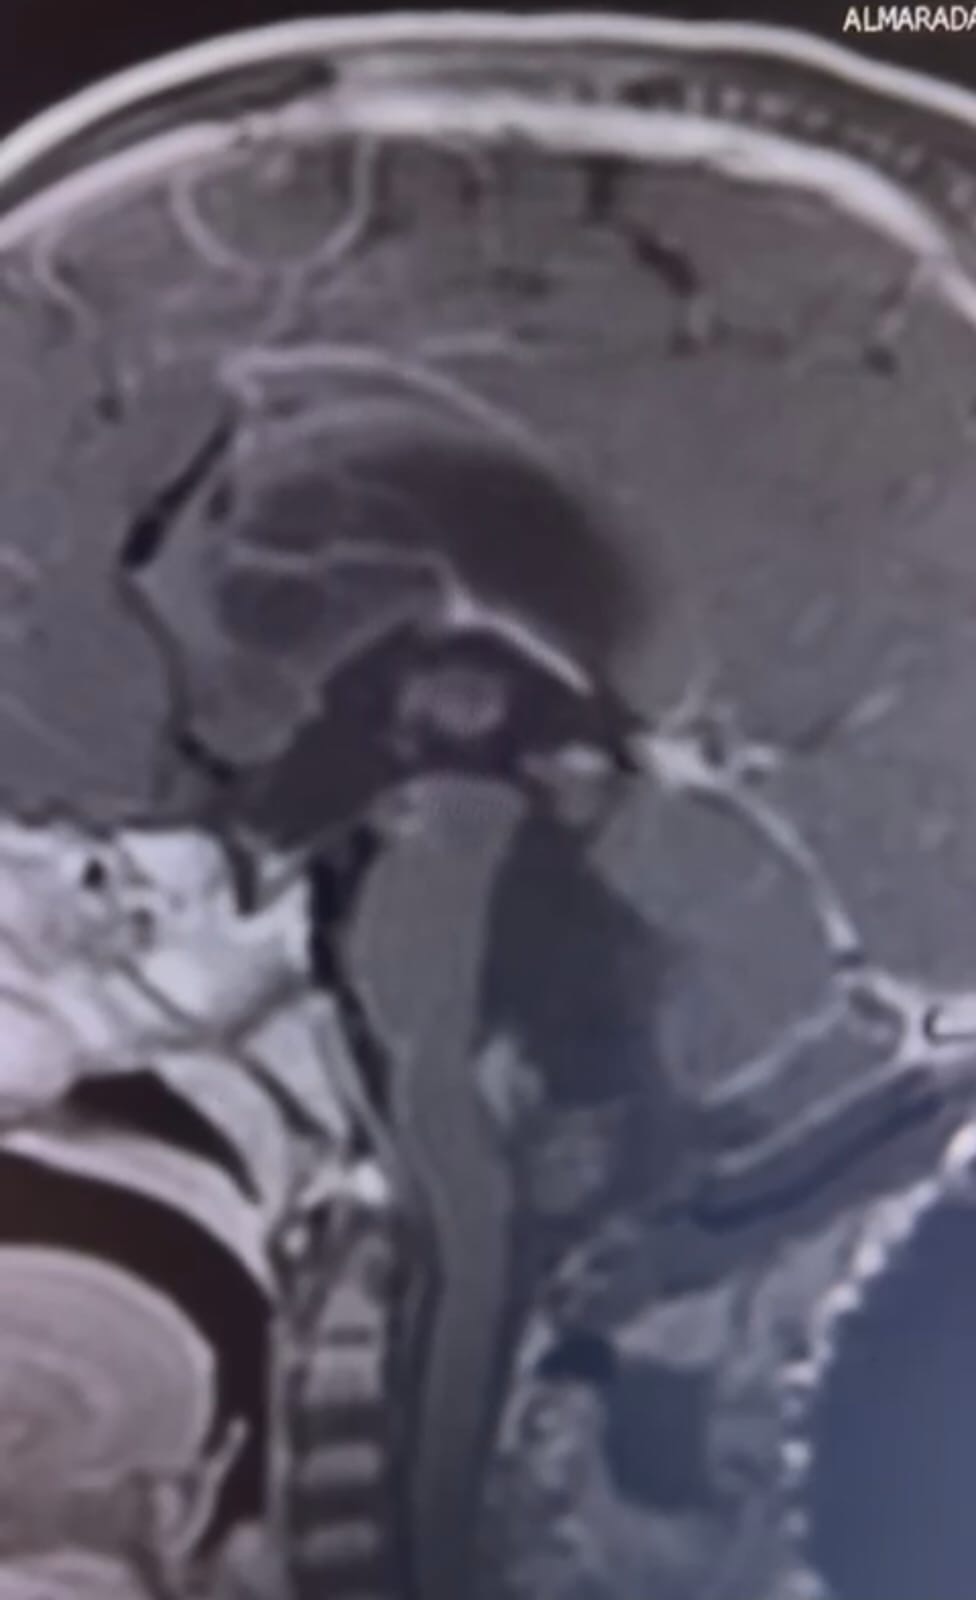

في سابقة هي الأولى من نوعها، تمكن فريق طبي متخصص في مستشفى الكرك الحكومي من إجراء عملية جراحية معقدة لإزالة ورم من رأس طفل. وقد تكللت العملية بنجاح، مما أدخل البهجة والسرور على قلب عائلة الطفل وكافة الكوادر الطبية في المستشفى.

وقاد العملية الاستشاري في جراحة قعر الجمجمة، الدكتور عامر العمري، بمساعدة فريق متكامل من الأطباء، الدكتور نضال أبو سدره والدكتور يوسف أبو نواس. استغرقت العملية نحو عشر ساعات، حيث تم استخدام تقنيات حديثة ودقيقة لضمان إزالة الورم بأمان ودون التأثير على الأنسجة المحيطة.